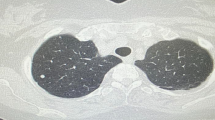

Lung cancer is the most common cause of cancer death in the world. What starts as an abnormal population of cells can, if caught in a curative stage, manifest radiographically as a pulmonary nodule. The early detection of lung nodules has shown to improve mortality and volumetric analysis may have an integral part of nodule management based on results of the NELSON study [1].

An estimated 1.6 million new pulmonary nodules will be detected by chest CT scans annually in the USA [2]. Most detected nodules are benign and it is often difficult to radiographically distinguish those that are malignant, leading to the need for biopsies. Transthoracic biopsies and surgical resection have high diagnostic yield but more complications than bronchoscopy, including pneumothorax or surgical morbidities that increase the costs of the procedures. Unfortunately, conventional bronchoscopy is notoriously poor at reliably diagnosing peripheral pulmonary nodules, particularly for those that are small, do not have an airway clearly leading to them (bronchus sign on computed tomography), are benign, and display a host of other factors. A recent prospective, randomized controlled trial comparing conventional bronchoscopy with fluoroscopic guidance to that using a thin bronchoscope and radial endobronchial ultrasound (EBUS) failed to show a statistically significant diagnostic difference between groups in patients with peripheral pulmonary lesions 1.5–5 cm in size [3]. Bronchoscopy was only diagnostic in 44% of patients with peripheral lesions in that study. Limitations to successful biopsy may include the ability to reach into the lung periphery and control or precision at the time of biopsy. Improved instrument stabilization at the time of biopsy may improve the diagnostic yield, particularly when an eccentric as opposed to concentric view is obtained by radial EBUS.

Various technologic advances have been developed with the intent of improving the diagnostic yield of bronchoscopy. For peripheral lesions, these include the use of navigational systems, thin and ultrathin bronchoscopy, radial endobronchial ultrasound, radiographic airway reconstruction, virtual bronchoscopy, bronchoscopic transparenchymal nodule access, and use of cone beam CT. While providing an improved diagnostic yield over non-guided bronchoscopic techniques, the accuracy remains close to 70%, far below the 90–95% yield of transthoracic biopsies [4]. The prospective NAVIGATE study was a multi-center cohort study that evaluated the use of the superDimension navigation system (Medtronic, Minneapolis, MN). The median lesion size was 20.0 mm of 1215 subjects in 29 centers. The 12-month diagnostic yield was 73% [5]. The AQuIRE quality improvement registry reported a diagnostic yield using electromagnetic navigational (EMN) bronchoscopy of only 38.5% [6]. A recent meta-analysis reported a sensitivity of 77% [7]. The use of cone beam CT and augmented fluoroscopy is beyond the scope of this article but entails new technologic advances regarding the diagnosis of peripheral pulmonary lesions [8]. However, the prevalence of lung nodules and current limitations of diagnostic techniques highlight the need for improvements, and robotic bronchoscopy may provide some solutions.